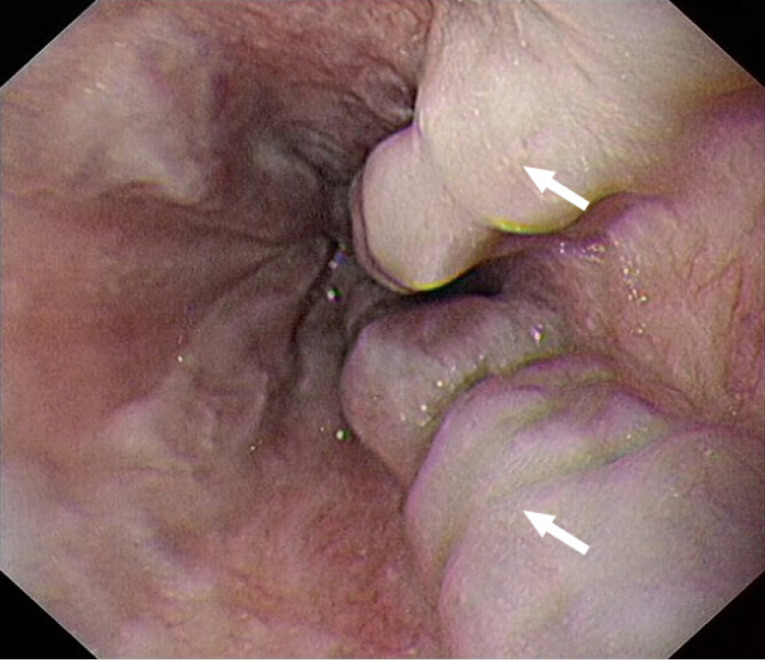

Case summary: A 36-year-old male patient presented with massive ascites. Laboratory tests revealed pancytopenia and a serum-ascites albumin gradient greater than 1.1 g/dL. An abdominal computed tomography scan demonstrated cirrhosis, splenomegaly, pancreatic fat infiltration, and a substantial accumulation of peritoneal fluid. Gastroscopy identified esophageal varices. Liver stiffness measurement indicated a value of 32.7 kPa. Based on the results of auxiliary examinations, common causes of cirrhosis were excluded, and a mutation in the Shwachman-Bodian-Diamond syndrome gene was ultimately identified through whole-exome sequencing. The patient was diagnosed with cirrhosis secondary to SDS. Following the correction of hypoalbuminemia and administration of diuretics, the patient's ascites resolved.